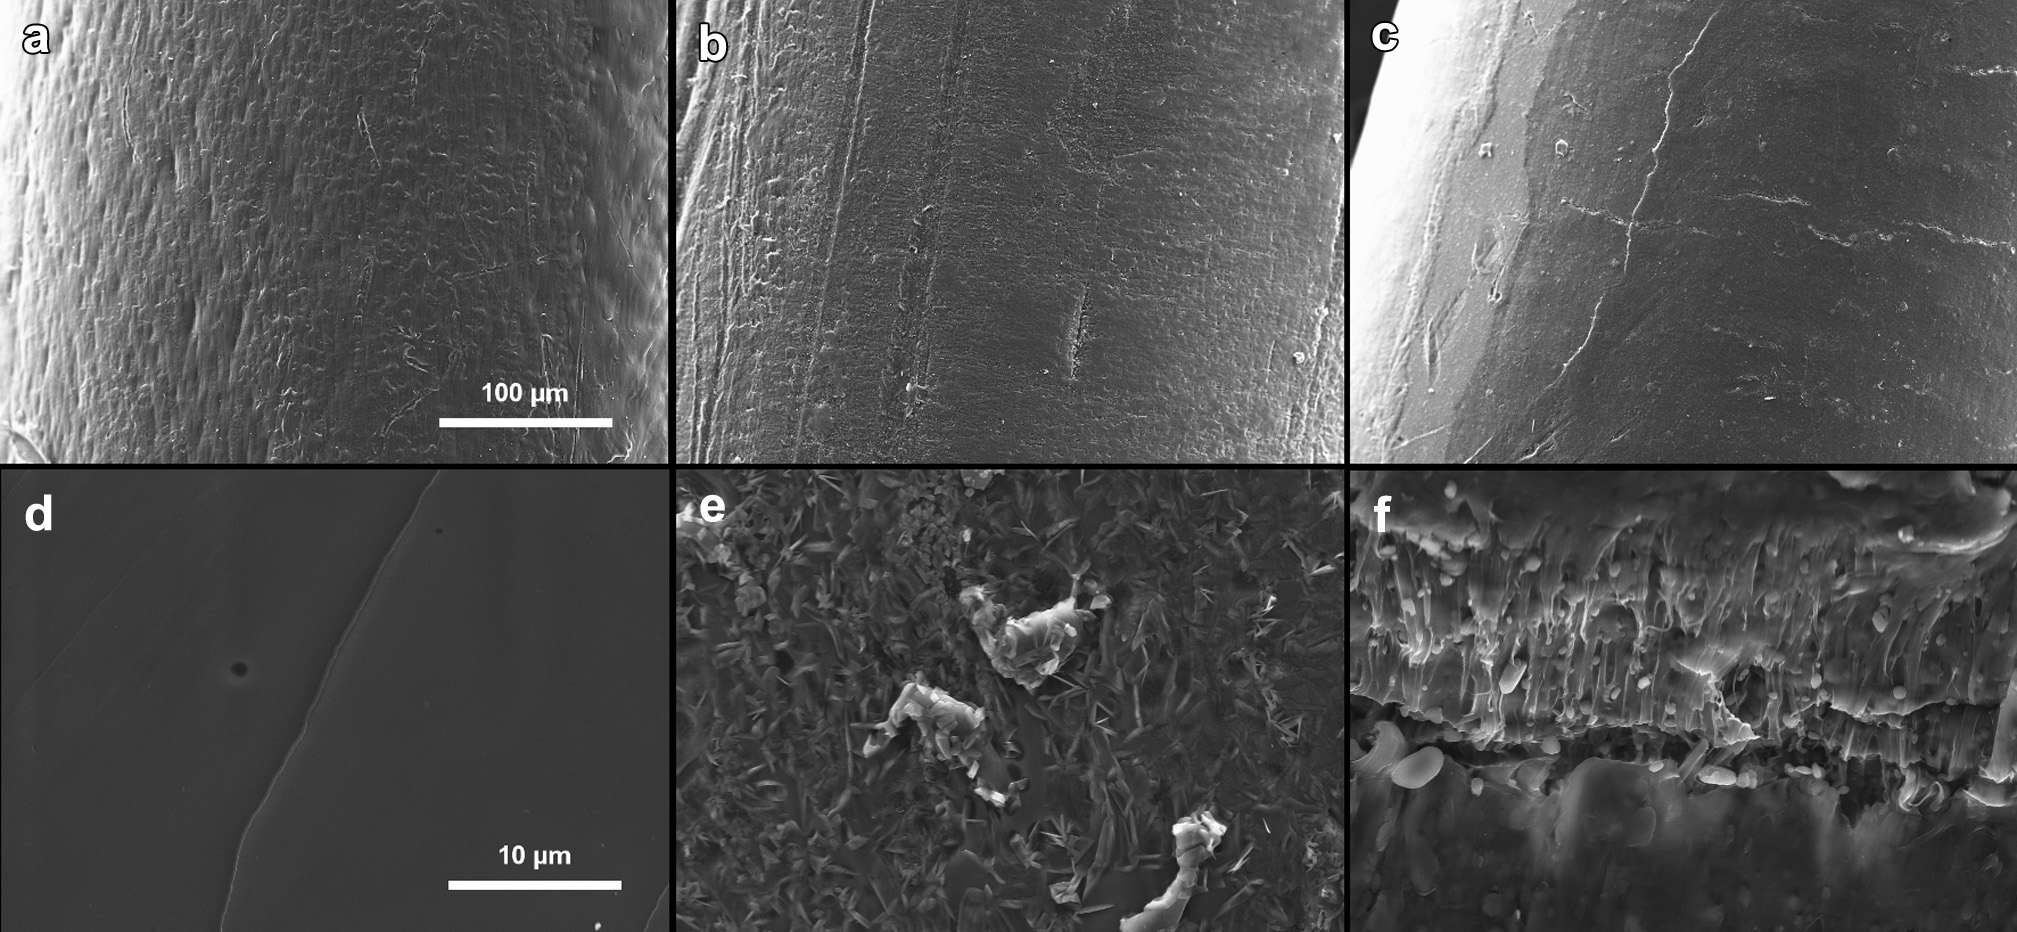

采用扫描电子显微镜(SEM;LEO Gemini,德国奥伯科亨)研究了热熔挤出丝材及3D打印原型在释放实验前后表面和横截面的形貌。样品在分析前使用真空蒸发仪进行碳涂层处理。获取SEM图像时采用的加速电压为8 kV和15 kV。

用于制造PCLfilaments的HME过程在100°C下进行,该温度高于 PCL的熔点但低于吲哚美辛的熔点(160°C,对应于稳定g‐型吲哚美辛)。在加工温度低于药物熔点的HME过程中,固体药物作为溶质,而聚合物则作为黏性溶剂。药物逐渐溶解到聚合物熔体中,形成药物e聚合物固体分散体。药物颗粒完全减小,或直至达到加工温度下药物在聚合物中的溶解度极限。PCL的溶解度参数为19.1–19.3 MPa¹/²,而吲哚美辛的溶解度参数为22.1 MPa¹/²(按Hoftyzer/Van Krevelan和Hoy溶解度参数的平均值计算),两者之间相差2.8–3.0 MPA¹/²。根据 Greenhalgh等人 的观点,若差值小于7 MPa¹/²,则化合物至少表现出一定的相容性。数值越接近,相容程度应越高。因此可以推断,吲哚美辛在HME过程中至少能在一定程度上溶解于熔融的PCL中。进一步的研究,例如DSC,证实了这一结论。对约3个月大的filaments进行了 SEM分析,以进一步了解样品的形态(图4)。结果显示,无药物及载药量高达15%的filaments表面相对光滑且致密,而在载药量最高的丝材表面则可见一些裂纹。载药丝材横截面的质地不如无药物丝材那样光滑,这是由于丝材内部存在细小的药物颗粒所致。

根据扫描电镜分析,所有打印原型的表面均显示出层状结构(图5)。无药物和5%载药原型的横截面光滑。在5%载药原型的横截面上可以看到一些药物颗粒。观察到的药物晶核(尺寸为<1 mm)可能是由于未溶解和/或重结晶药物的存在,因为扫描电镜分析是在存放2个月的样品上进行的。30%载药原型的横截面因存在晶体药物而不平整。

HME丝材与3D打印原型之间在表面和横截面形貌上的差异可能对药物释放速率产生显著影响,因为3D打印原型的层状结构具有更大的表面积,有利于药物溶解和吸水,而丝材的表面相对均匀且呈整体性。